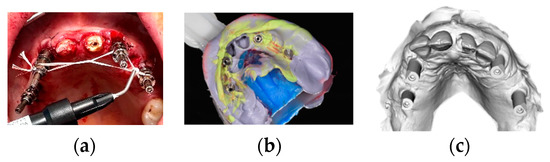

A full thickness flap was raised from molar to molar, and flap elevation was extended on the buccal sides of the maxilla and the mandible, isolating and preserving the anatomical structures. Minimal ostectomy was performed when necessary to compensate for bone discrepancies (Figure 2).

Figure 2.

(a) Intraoral pictures of a mandibular case after teeth extraction and flap elevation; (b) a minimal ostectomy was performed in order to compensate for bone discrepancies.